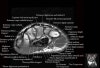

- Axial section

Axial T1 evaluates the tendons of the wrist and carpal tunnel, including the flexor retinaculum.